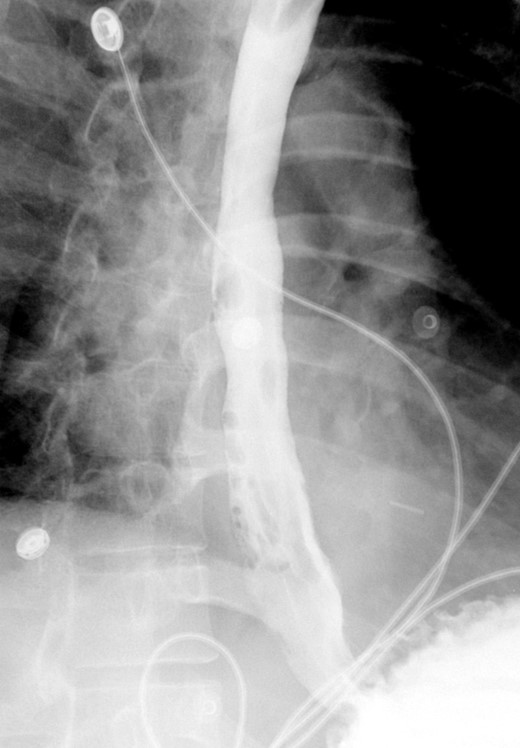

A computed tomographic scan revealed air and fluid surrounding the esophagus (Fig. 1). Esophagogram performed with water-soluble contrast media showed a distal esophageal perforation with a free leak into a large mediastinal cavity to the left of the esophagus (Fig. 2). The patient was triaged directly to the operation room. A left chest tube was placed with improvement in his oxygenation, and grossly murky fluid was drained. Esophagogastroduodenoscopy (EGD) was performed next and revealed a very small caliber esophagus with concentric ringed appearance. A tight stricture was noted in the mid-esophagus, which only allowed passage of a pediatric gastroscope. In the lower esophagus, a 2-cm tear with necrotic edges was visualized 3 cm above the gastroesophageal (GE) junction. With this diffusely strictured and very diseased appearance of the esophagus, the decision was made to proceed with stent placement and thoracoscopic drainage of the mediastinum rather than primary surgical repair via thoracotomy. A fully covered, 15 cm × 19 mm, EndoMAXX® esophageal stent was successfully placed covering the perforation site. Mediastinal washout and drainage was performed subsequently via left thoracoscopy. A postoperative esophagram showed no leak and the patient was started on a liquid diet that was tolerated well. His hospital stay was uneventful, and he was discharged on twice daily high-dose proton pump inhibitor (PPI) on post-operative Day 5. He was placed on a mechanical soft diet on discharge. Repeat upper GI study with water soluble contrast postoperatively showed no evidence extravasation. (Fig. 3)

Demonstrates narrow esophageal caliber and extensive distal left thoracic esophageal leak approximately 3 cm proximal to the GE junction.